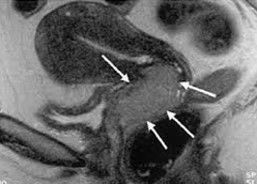

El cáncer cervical o cáncer de cérvix está incluido dentro de las neoplasias que afectan al cuello del útero (cérvix) y se proyectan al interior del útero o vagina.Lesiones Precursoras: CIN I: Displasia presente solo en el tercio inferior del epitelio. CIN II: Displasia en los dos tercios inferiores del epitelio. CIN III: Displasia presente y de espesor total en el epitelio

Caption: : Muestra histológica de cuello uterino sano.